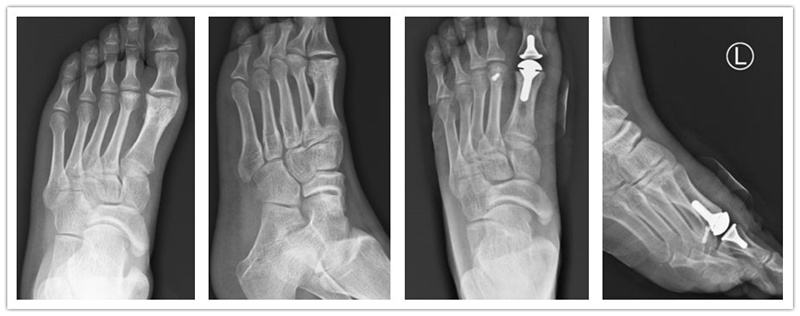

兰大二院骨科四病区完成甘肃省首例人工生物金属聚乙烯假体全关节跖趾关节置换术

近日,在北京大学人民医院徐海林主任的指导下,我院骨科四病区副主任刘京升带领副主任医师王凯、冯凯完成了甘肃省首例人工生物金属聚乙烯假体全关节跖趾关节置换术。

患者,男性,43岁。自诉行走时前足疼痛2年余,就诊于多家医院均无法明确诊治,经我院骨科四病区医护团队的仔细查体及影像学分析,明确诊断为踇僵硬。完善相关检查后,骨科四病区进行了全体讨论,并结合最新的足踝外科领域进展,决定为其实施人工生物金属聚乙烯假体全关节跖趾关节置换术。术中一切顺利,术后恢复良好,效果满意。

踇僵硬是以第一跖趾关节疼痛和活动受限为特征的关节退行性病变。早期症状主要包括疼痛、肿胀和跖趾关节滑膜炎,背伸受限则是其中最典型的特征一。此类患者常诉步态僵硬,第一跖趾关节局部疼痛,在步行和站立时加重,休息后缓解。临床上常采用关节唇切除术、关节成形术、第一跖骨截骨术、跖趾关节融合术等,但这些传统术式解决踇僵硬引起疼痛的同时,一定程度上牺牲了正常跖趾关节的功能活动。1974年Swanson采用医用新型高强度硅胶弹性材料设计制作了双柄铰链式硅胶假体,该假体柔韧性强,生物相容性好,较为耐用,但是随着时间进展,硅胶假体常出现骨质溶解等影像学表现,最终发展成临床并发症,需要二期翻修。此后金属植入物由此发明,但是当第一跖趾关节疾患到达晚期,病变累及双侧关节面时,需要置换整个跖趾关节,金属半关节假体已无法满足临床需求,此时临床学者发明了人工生物金属聚乙烯全关节假体。

近年来,我国逐渐采用人工生物金属聚乙烯假体全关节置换术,此类手术创伤小、并发症少、疗效较确切。随着我院骨科专业化的发展及与国内外的积极探索交流,我院也积极开展此类手术。此例手术的成功,标志着我院骨科在足踝外科领域已达到国内先进水平。